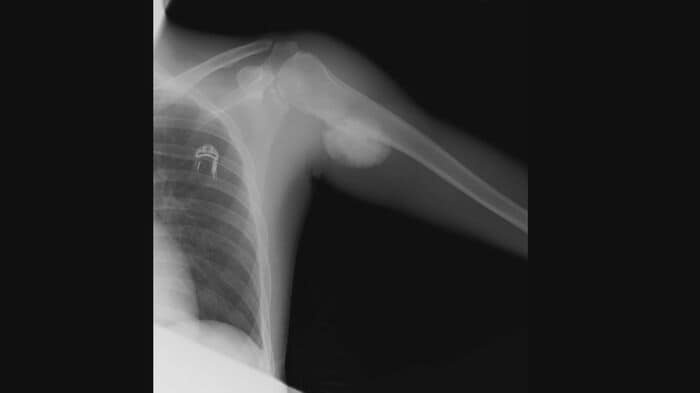

骨の一部を切断し、悪性組織の周りを液体窒素で消滅させるという大手術は、13時間に及んだ。いま、肩には「人工関節」が入っている。

自分の骨をできるだけ残して、戻す方法にしようかって話になって。骨をごっそりとるよりは、危なくなる所が出る可能性があるので、再発のリスクは少し上がるかもという話で手術したんですよね